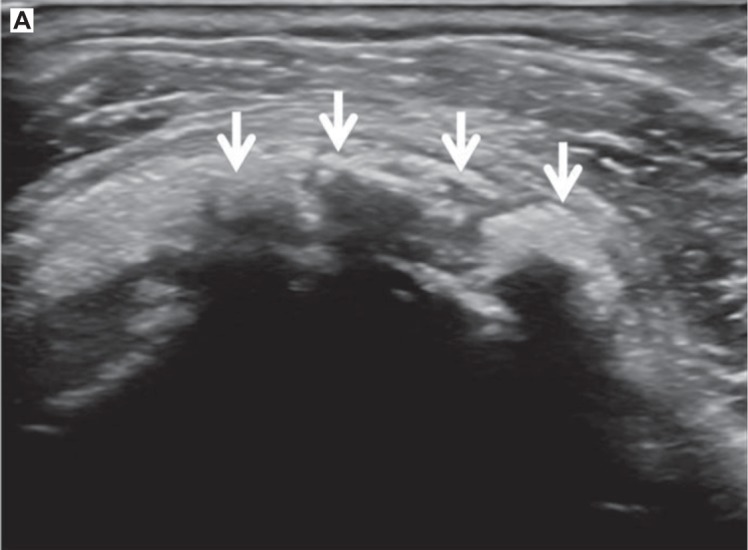

Sombra acústica

La sombra acústica es ese “vacío” oscuro que aparece por debajo de una estructura que bloquea el haz. Se ve como una zona hipoecoica o negra porque el sonido no llega con suficiente energía a lo que hay detrás.

Suele aparecer cuando el tejido atenúa mucho el ultrasonido o cuando actúa como un reflector muy potente. Por eso es típica bajo la cortical ósea y también bajo calcificaciones.

A continuación, te ponemos 2 ejemplos prácticos extraídos del artículo de Chingkoe et al (referencia 1 de la bibliografía de este artículo):

A nivel clínico tiene una doble cara. Cuando ves un foco hiperecogénico con una sombra por debajo, suele indicar una estructura dura (hueso o calcificación) y eso orienta. El problema es que esa misma sombra puede ocultar el tejido que hay debajo. Por ejemplo, una calcificación puede dificultar la visualización del tendón profundo y hacer que una rotura parcial pase desapercibida.

La forma práctica de reducir errores, a menudo consiste en inclinar ligeramente la sonda y buscar otra trayectoria del haz que “bordee” el obstáculo. Si además ajustas el foco a la profundidad real del objetivo y confirmas la imagen en dos planos, minimizas muchísimo el riesgo de confundir una sombra con un defecto real del tejido.